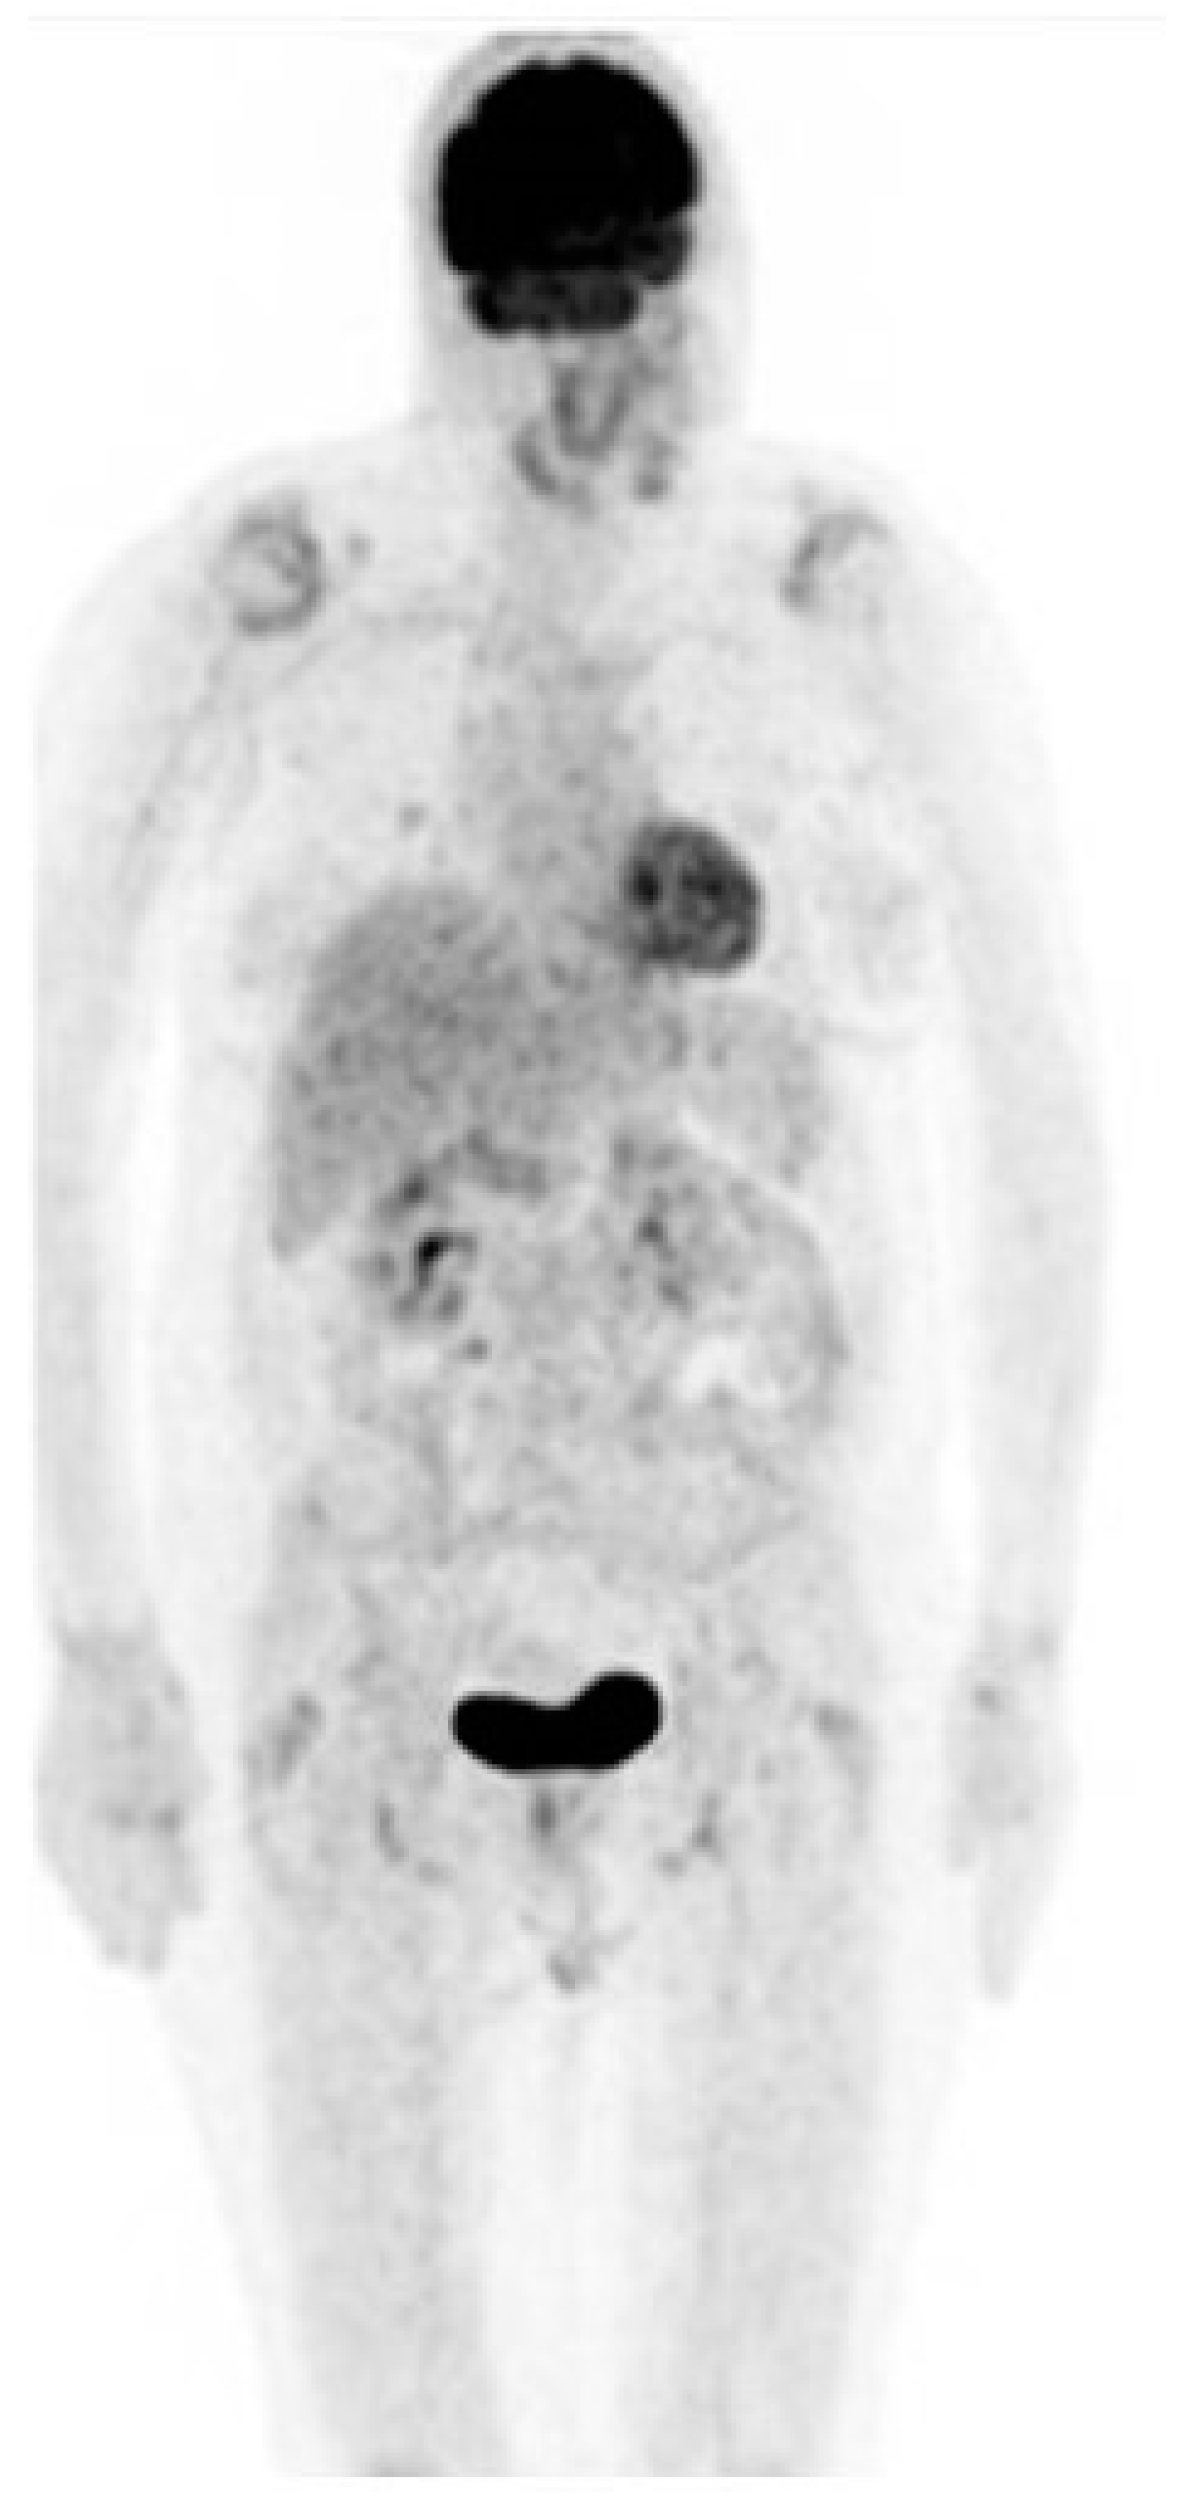

On 19 December 2017, a biopsy of the nevus revealed metastatic malignant melanoma and a subsequent total body PET–CT scan revealed hyper metabolic absorption in the vertebral bodies and soft tissue at levels D5, D7, and D9 (the area of the nevus), consistent with malignant disease (Figure 1).

Figure 1. PET–CT scan showing hypermetabolic absorption in the vertebrae area (red arrow).